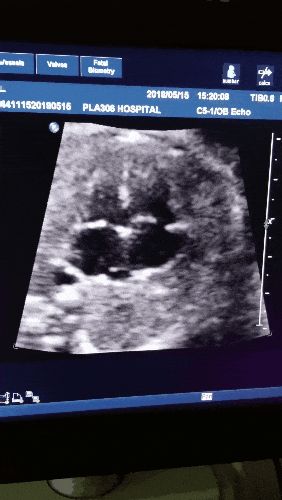

当你第一次在B超屏幕上

看到那个小豆丁扑通扑通的心跳